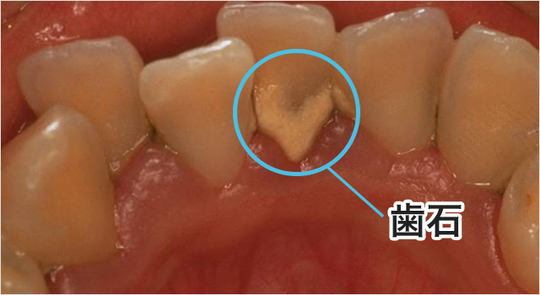

歯石とは

歯石とは歯垢(プラーク)が硬くなったものです。 歯磨きで除去できなかった歯垢が、唾液の中のミネラルと結合して、硬くなって生じます。 歯についた歯垢は、2日間ぐらいで歯石になります。 歯と歯ぐきの境い目や歯と歯の間に生じた硬い歯石は、石の様に硬くなっているので歯磨きだけでは取り除くことが出来ません。